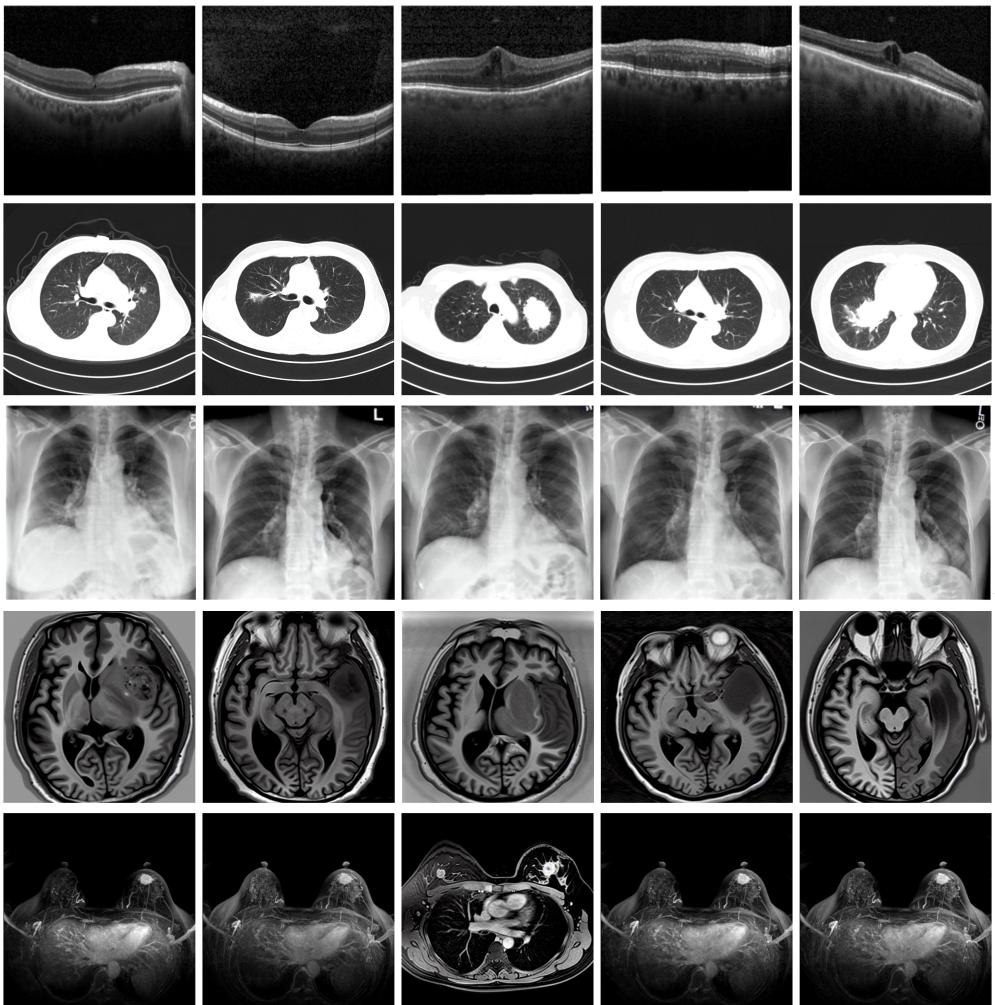

圖為由MINIM生成的高質(zhì)量醫(yī)學(xué)合成圖像(受訪者供圖)

“目前公開的醫(yī)學(xué)影像數(shù)據(jù)非常有限,我們建立的生成式模型有望解決訓(xùn)練數(shù)據(jù)不夠的問(wèn)題?!北本┐髮W(xué)未來(lái)技術(shù)學(xué)院助理研究員王勁卓說(shuō),研究團(tuán)隊(duì)利用多種器官在CT、X光、磁共振等不同成像方式下的高質(zhì)量影像文本配對(duì)數(shù)據(jù)進(jìn)行訓(xùn)練,最終生成海量的醫(yī)學(xué)合成影像,其在圖像特征、細(xì)節(jié)呈現(xiàn)等多方面都與真實(shí)醫(yī)學(xué)圖像高度一致。

實(shí)驗(yàn)結(jié)果顯示,MINIM生成的合成數(shù)據(jù)在醫(yī)生主觀評(píng)測(cè)指標(biāo)和多項(xiàng)客觀檢驗(yàn)標(biāo)準(zhǔn)方面達(dá)國(guó)際領(lǐng)先水平,在臨床應(yīng)用中具有重要參考價(jià)值。在真實(shí)數(shù)據(jù)基礎(chǔ)上,使用20倍合成數(shù)據(jù)在眼科、胸科、腦科和乳腺科的多個(gè)醫(yī)學(xué)任務(wù)準(zhǔn)確率平均可提升12%至17%。